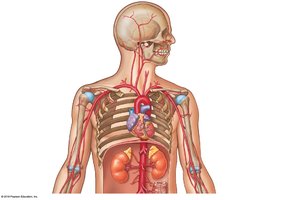

Major Systemic Arteries

Oxygenated blood leaves the left ventricle through the aortic valve into the ascending aorta, aortic arch, and descending aorta. Major branches include:

Brachiocephalic trunk: Right common carotid and right subclavian arteries

Left common carotid artery

Left subclavian artery

Circulation to the Brain

Blood supply to the brain is provided by the internal and external carotid arteries and vertebral arteries. The Cerebral Arterial Circle (Circle of Willis) ensures continuous blood flow to the brain.